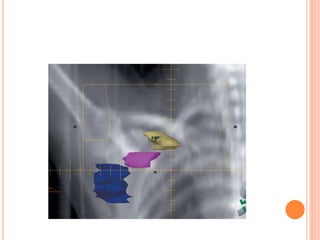

LOCALIZATION OF LUMPECTOMY CAVITY

 Pre-op clinical finding , pictures

 Imaging- mammogram,usg,MRI

 Per-op finding

 HPR

 Surgical clips

 Post op imaging with USG,CT or MRI

Use of mammography in defining

the boost target localisation in

breast conserving treatment